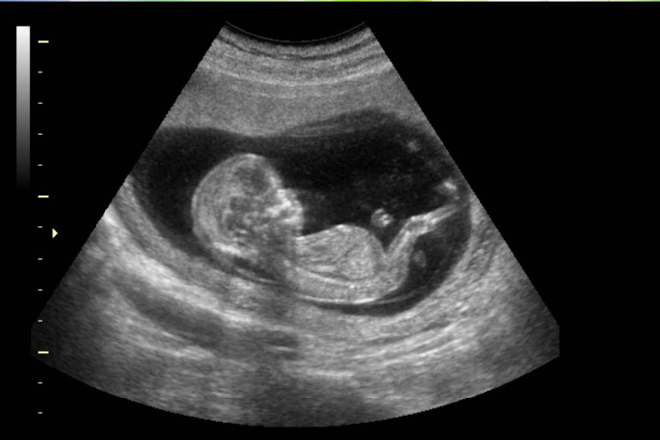

¿Se asocia la ecografía prenatal con los trastornos del espectro autista (TEA)?

Los hallazgos de este estudio son en general consistentes con datos previos que sugieren que la ecografía prenatal no es un factor causal suficiente de los TEA. Sin embargo, no se descarta su potencial como un factor de estrés ambiental en un sistema genéticamente vulnerable. JAMA Pediatrics, 12 de febrero de 2018